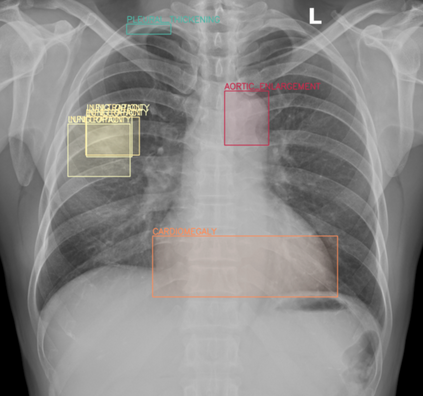

Transfer learning (TL) with deep convolutional neural networks (DCNNs) has proved successful in medical image classification (MIC). However, the current practice is puzzling, as MIC typically relies only on low- and/or mid-level features that are learned in the bottom layers of DCNNs. Following this intuition, we question the current strategies of TL in MIC. In this paper, we perform careful experimental comparisons between shallow and deep networks for classification on two chest x-ray datasets, using different TL strategies. We find that deep models are not always favorable, and finetuning truncated deep models almost always yields the best performance, especially in data-poor regimes. Project webpage: https://github.com/sun-umn/Transfer-Learning-in-Medical-Imaging Keywords: Transfer learning, Medical image classification, Feature hierarchy, Medical imaging, Evaluation metrics, Imbalanced data